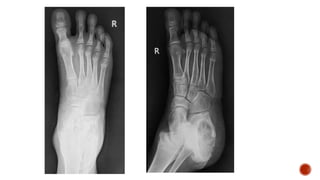

 Foot radiographic views

 Radiological signs

 Types of periosteal reaction

 Dorsoplantar radiograph of the foot shows destruction of the head of the 5th

metatarsal and the base of the proximal phalanx of the 5th toe with apparant

widening of teh joint space.

 Foot radiograph :

 Dorsoplantar: metatarsals in neutral position

 Medial: DP projection with the foot angled 30-40° medially

 Lateral

 Weight bearing